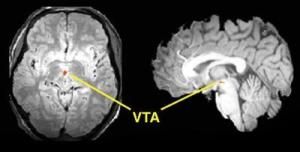

3.MRI檢查

腦幹膠質細胞瘤常呈長T1和長T2信號改變,多無囊變或出血,邊界一般不清,形態不規則,多數腫瘤有Gd-DTPA增強。與CT掃描相比,由於其多視角成像及無顱底骨偽影干擾,能更清晰地顯示病變部位及範圍。海綿狀血管瘤在出血的急性期T1Wl及T2Wl上皆為均勻的高密度,輪廓清晰,常呈圓形,在亞急性及慢性期T1Wl及T2W1上也皆為高密度。室管膜瘤為長T1,長T2,向腦幹外發展至第四腦室或小腦腦橋角,血管網狀細胞瘤為長T1及長T2,球形位於延髓後方。結核球為環形高密度,加強後更顯著,中間為低密度。